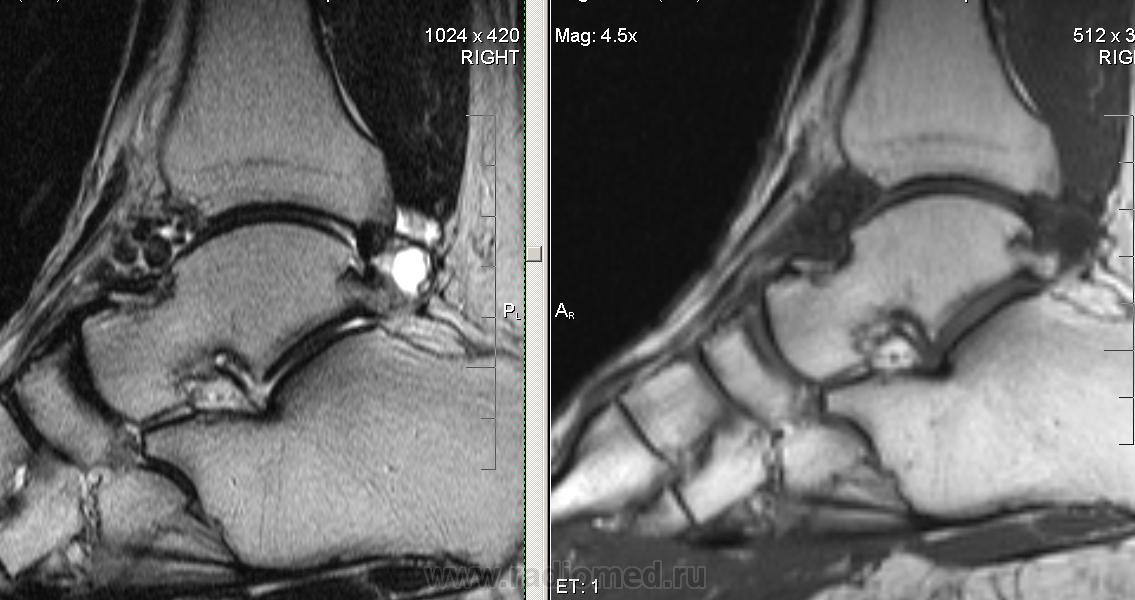

Пол пациента: Мужской пол Тип патологии: Доброкачественное новообразование, киста Область исследования: Скелетно-мышечная система Методы исследования: МРТ Мужчина, 1956г.р. 8 лет назад травма сустава (подвернул при прыжке с грузовой машины). Беспокоят умеренные боли при движении. https://radiomed.ru/sites/default/files/styles/case_slider_image/public/user/7985/golenost2.jpg?itok=3vQGkog- https://radiomed.ru/sites/default/files/styles/case_slider_image/public/user/7985/golenost3.jpg?itok=HPR_hh_5 https://radiomed.ru/sites/default/files/styles/case_slider_image/public/user/7985/golenost4.jpg?itok=iZwbAjxO ID:25824 Пнд, 21/01/2013 - 22:48 #1 irena Не на сайте Был на сайте: 9 лет 7 месяцев назад Зарегистрирован: 28.09.2009 - 13:00 Публикации: 289 Он самый. Красиво. Втр, 22/01/2013 - 12:17 #2 Helios Не на сайте Был на сайте: 7 месяцев 2 недели назад Зарегистрирован: 06.08.2010 - 15:16 Публикации: 4417 Более всего похоже на хондроматоз .

Более всего похоже на хондроматоз